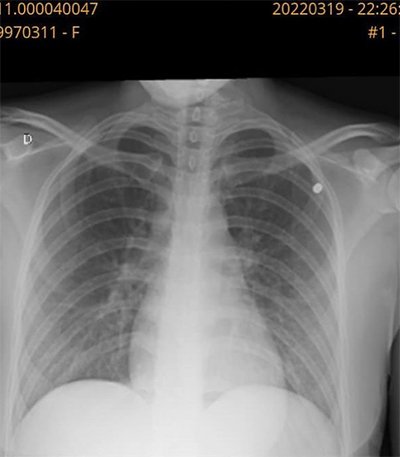

Radiografia feita por Rafaela no sábado (19/3) mostra projétil alojado no tórax

Ao jornal O Dia, Rafaela diz que foi ao Hospital Glória D’Or e foi informada que, ao toque, era possível sentir um objeto dentro de seu corpo. A radiografia comprovou que um pequeno projétil estava alojado no tórax da jovem.